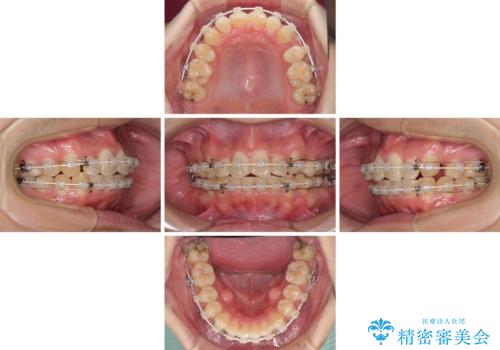

- 矯正装置

- 審美装置

結婚式前には目立つ部分の装置を一時的に外し、結婚式後に装着し直して治療を継続する予定としました。

咬合力が非常に強く、抜歯したスペースがなかなか閉じないであろうことは予想できましたが、思っていた以上に期間がかかりました。

前歯のすり減りも著しかったため、仕上げの位置の調整にも期間を要しました。